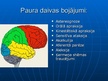

Smadzeņu pakauša, deniņu, paura un pieres daļas bojājumu neiropsiholoģiskie s...